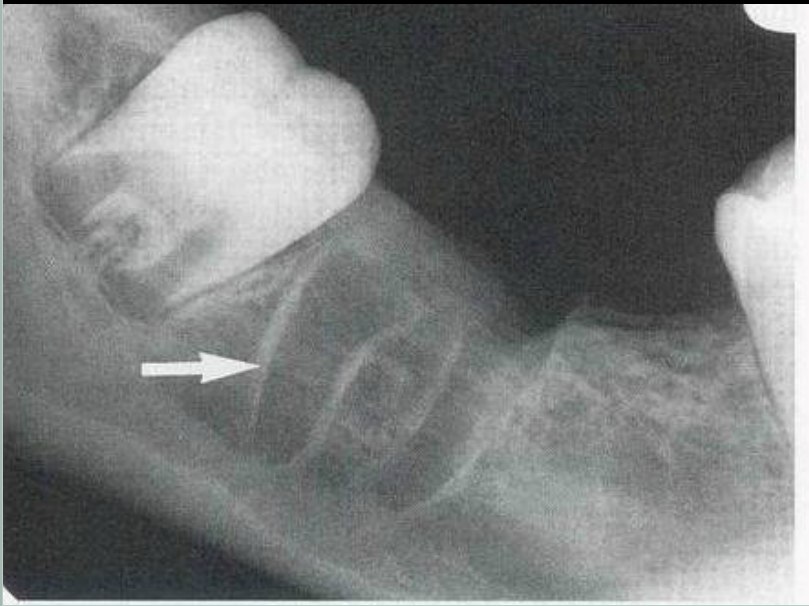

口腔頜面外科 影像技術(shù)